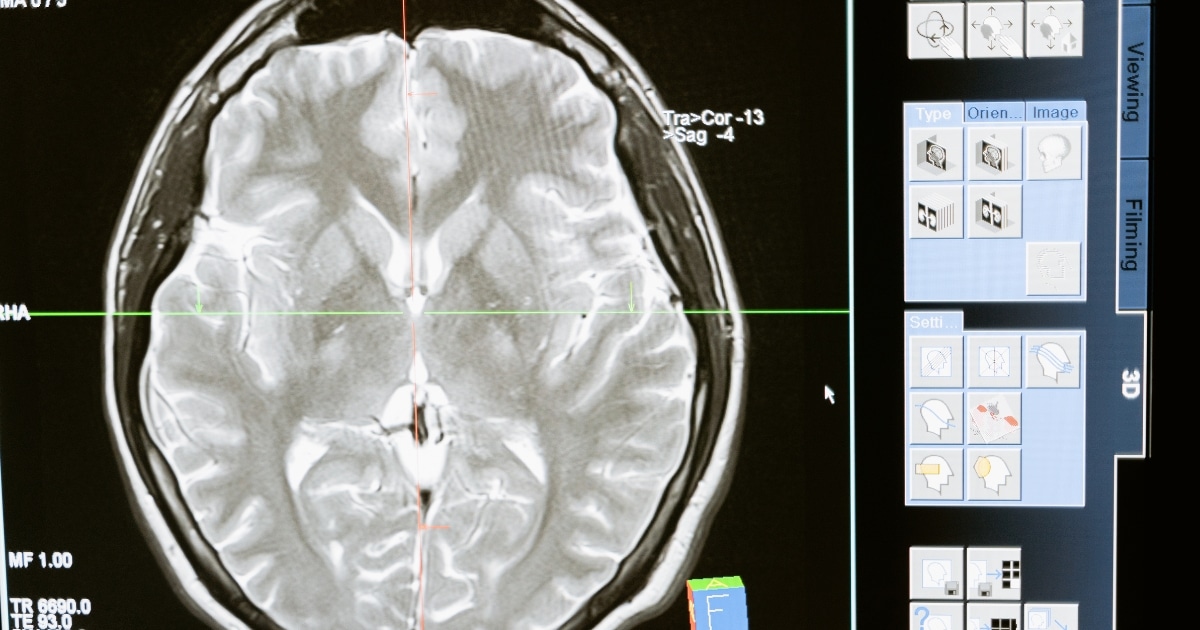

ปัจจุบันเราทราบกันดีแล้วว่า วิธีการที่จะป้องกันไม่ให้อาการของสมองเสื่อมโผล่ขึ้น แม้ว่าจะมีโปรตีนพิษเหล่านี้อยู่ในสมองแล้วก็ตาม ซึ่งขณะนี้เราสามารถตรวจจากเลือดได้แล้ว โดยไม่จำเป็นต้องเจาะน้ำไขสันหลัง หรือไปทำคอมพิวเตอร์สนามแม่เหล็กเอ็มอาร์ไอร่วมกับการตรวจทางเวชศาสตร์นิวเคลียร์เพ็ทสแกน